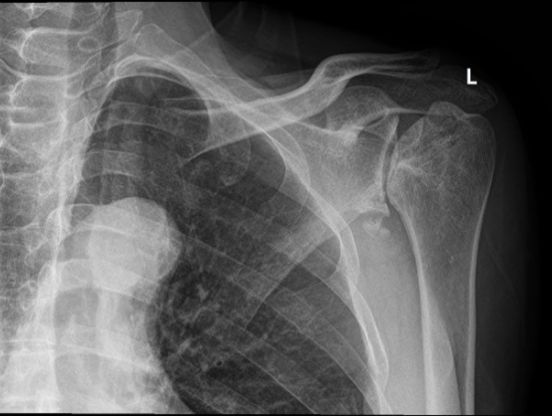

• 反肩关节置换治疗双侧重度肱骨头坏死

段鑫

成都市第一人民医院